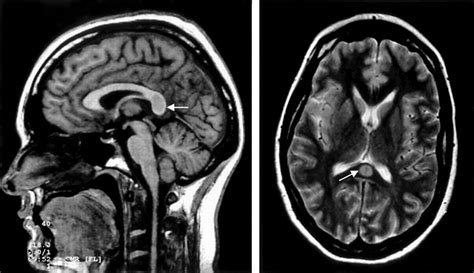

Due to its high concentration of neural pathways, the splenium of corpus callosum is a frequent area of interest in neuroradiology. Magnetic Resonance Imaging (MRI) is the gold standard for evaluating this region. Changes in the integrity of the splenium can be a marker for a variety of neurological conditions, ranging from developmental disorders to acute inflammatory processes.

When clinicians observe signal abnormalities in the splenium, they often look for what is termed "reversible splenial lesion syndrome" (RESLES). This condition often presents with acute onset of symptoms such as confusion, seizures, or vision changes, but interestingly, the lesions often resolve over time without permanent damage. This highlights the unique vulnerability and resiliency of the splenium to metabolic and inflammatory stressors.